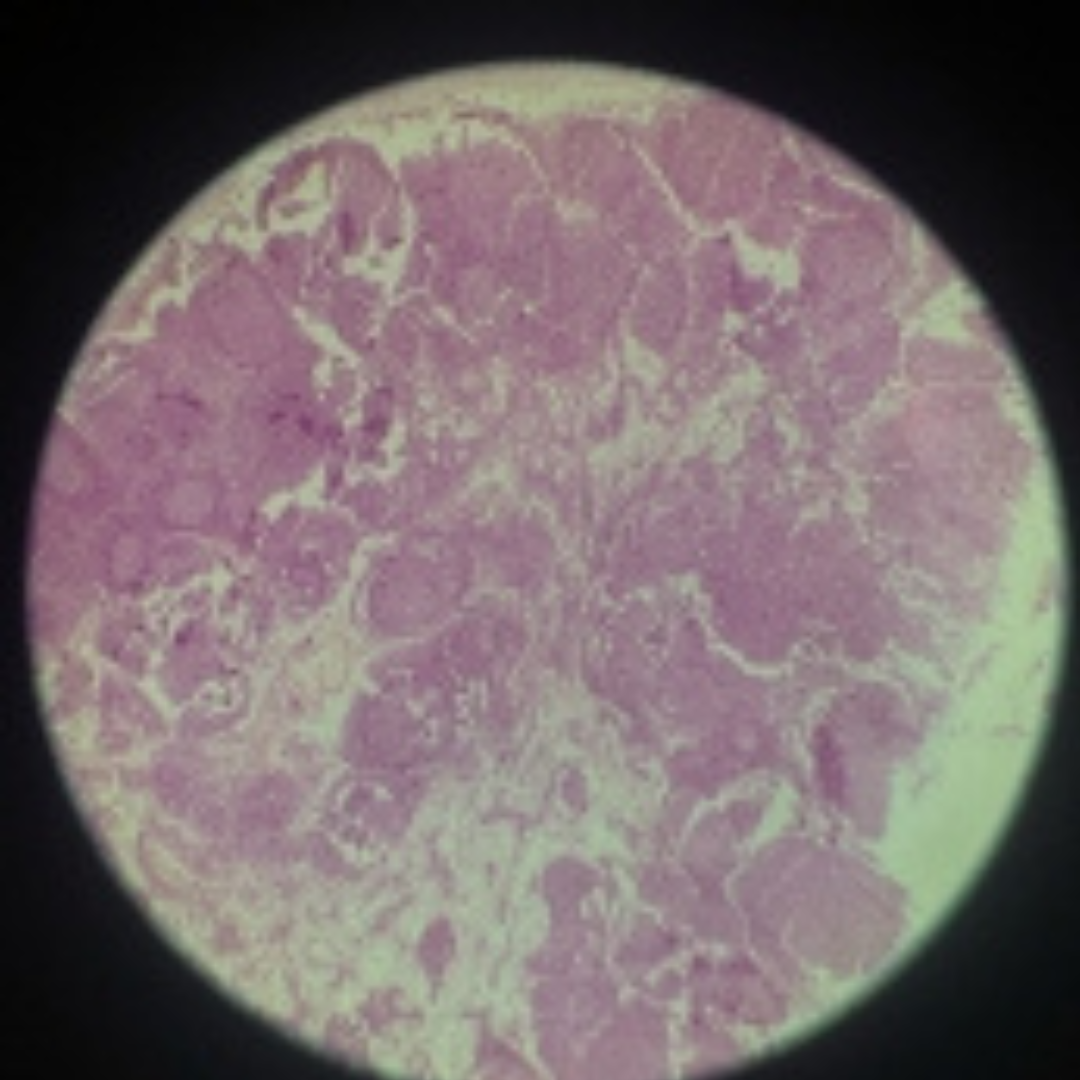

Spleen

21

New cards

Spleen

22

New cards

Spleen

23

New cards

Spleen

24

New cards

Spleen

25

New cards

Spleen

26

New cards

Spleen

27

New cards

Spleen

28

New cards

Spleen